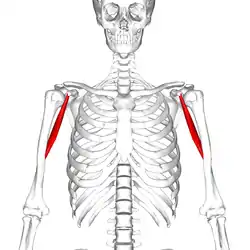

Position of coracobrachialis muscle (shown in red) | |

Position of coracobrachialis muscle (shown in red). Animation.

Position of coracobrachialis muscle (shown in red). Animation. Close up. Seen from below. Ribs are not shown.

Close up. Seen from below. Ribs are not shown. Still image. Lateral view.